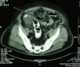

Perforated colon

Gastrointestinal perforation, also known as ruptured bowel, is a hole in the wall of part of the gastrointestinal tract. The gastrointestinal tract includes the esophagus, stomach, small intestine, and large intestine. [Source: Wikipedia ]